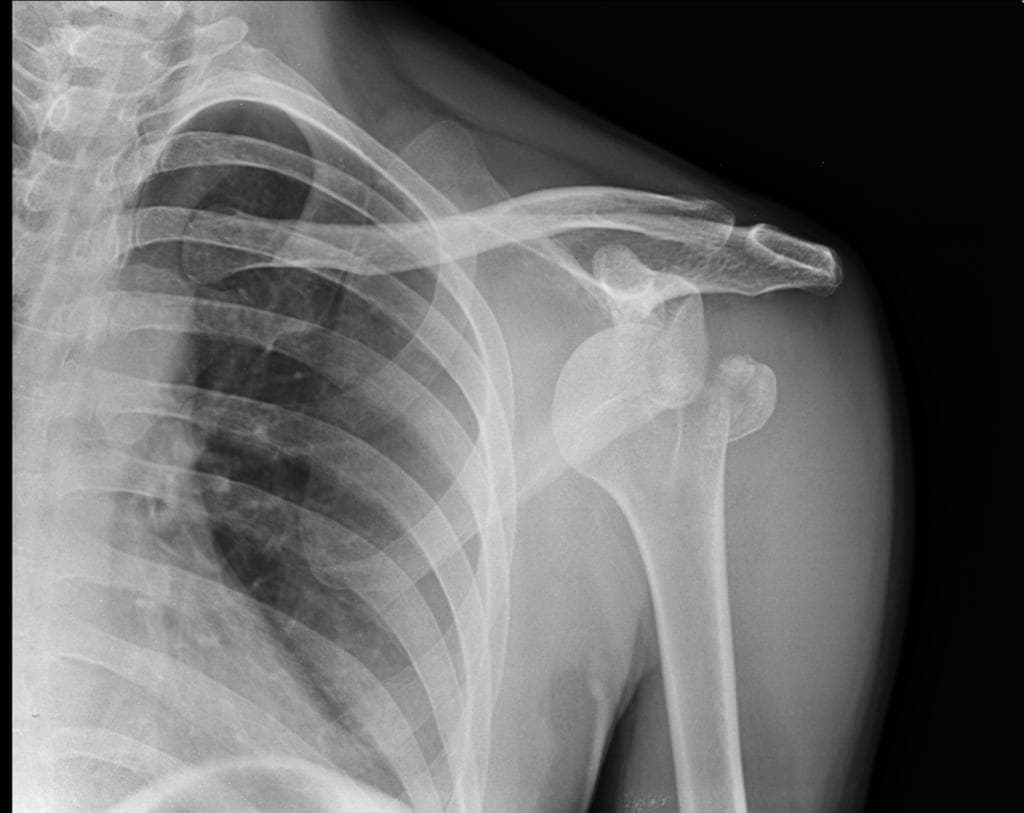

Bị chó nhà đụng phải, mất thăng bằng và ngã xuống đất. Cánh tay ở tư thế duỗi thẳng.

Chỏm xương cánh tay bị trật xuống dưới kèm gãy vụn đầu trên xương cánh tay và di lệch mấu động lớn. Lưu ý tư thế dạng của xương cánh tay. Hình ảnh X-quang sau nắn chỉnh tình trạng trật khớp vai. Không phát hiện tổn thương Bankart xương. Gãy vụn đầu trên xương cánh tay. THẢO LUẬN: Trật khớp vai xuống dưới, còn được gọi là luxatio erecta, là loại trật khớp vai ít gặp nhất. Trong trật khớp vai xuống dưới, cánh tay được giữ ở tư thế dạng do chỏm xương cánh tay bị kẹt dưới bờ xương ổ chảo. Trật khớp xuống dưới có thể giống với trật khớp vai ra trước kiểu dưới ổ chảo, trong đó chỏm xương cánh tay nằm ngay dưới mỏm ổ chảo của xương bả vai trên các bình diện thẳng và nghiêng.